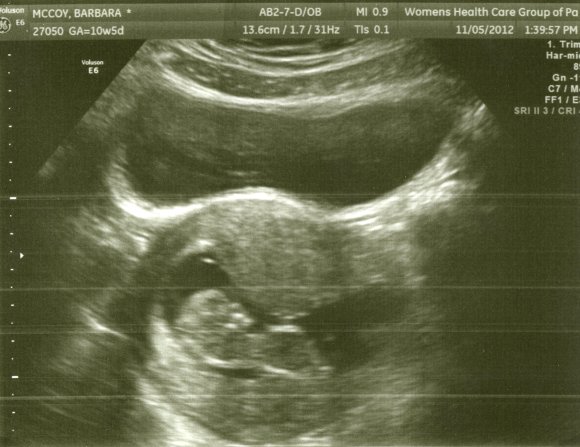

baby001